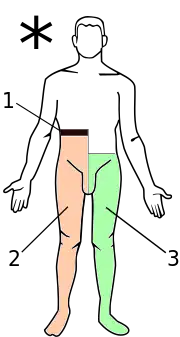

Brown-Séquard syndrome (also known as Brown-Séquard's hemiplegia, Brown-Séquard's paralysis, hemiparaplegic syndrome, hemiplegia et hemiparaplegia spinalis, or spinal hemiparaplegia) is caused by damage to one half of the spinal cord, i.e. hemisection of the spinal cord resulting in paralysis and loss of proprioception on the same (or ipsilateral) side as the injury or lesion, and loss of pain and temperature sensation on the opposite (or contralateral) side as the lesion. It is named after physiologist Charles-Édouard Brown-Séquard, who first described the condition in 1850.[1]

- The corticospinal lesion produces spastic paralysis on the same side of the body below the level of the lesion (due to loss of moderation by the UMN). At the level of the lesion, there will be flaccid paralysis of the muscles supplied by the nerve of that level (since lower motor neurons are affected at the level of the lesion).

- The lesion to fasciculus gracilis or fasciculus cuneatus (dorsal column) results in ipsilateral loss of vibration and proprioception (position sense) as well as loss of all sensation of fine touch.

- The loss of the spinothalamic tract leads to pain and temperature sensation being lost from the contralateral side beginning one or two segments below the lesion.

Brown-Séquard syndrome is an incomplete spinal cord lesion characterized by findings on clinical examination which reflect hemisection of the spinal cord (cutting the spinal cord in half on one or the other side). It is diagnosed by finding motor (muscle) paralysis on the same (ipsilateral) side as the lesion and deficits in pain and temperature sensation on the opposite (contralateral) side. This is called ipsilateral hemiplegia and contralateral pain and temperature sensation deficits. The loss of sensation on the opposite side of the lesion is because the nerve fibers of the spinothalamic tract (which carry information about pain and temperature) crossover once they meet the spinal cord from the peripheries.

Brown-Séquard syndrome is characterized by loss of motor function (i.e. hemiparaplegia), loss of vibration sense and fine touch, loss of proprioception (position sense), loss of two-point discrimination, and signs of weakness on the ipsilateral (same side) of the spinal injury. This is a result of a lesion affecting the dorsal column-medial lemniscus tract, well localized (deep) touch, conscious proprioception, vibration, pressure and 2-point discrimination, and the corticospinal tract, which carries motor fibers. On the contralateral (opposite side) of the lesion, there will be a loss of pain and temperature sensation and crude touch 1 or 2 segments below the level of the lesion via the Spinothalamic Tract of the Anterolateral System. Bilateral (both sides) ataxia may also occur if the ventral spinocerebellar tract and dorsal spinocerebellar tract are affected.

Crude touch, pain and temperature fibers are carried in the spinothalamic tract. These fibers decussate at the level of the spinal cord. Therefore, a hemi-section lesion to the spinal cord will demonstrate loss of these modalities on the contralateral side of the lesion, while preserving them on the ipsilateral side. Upon touching this side, the patient will not be able to localize where they were touched, only that they were touched. This is because fine touch fibers are carried in the dorsal column-medial lemniscus pathway. The fibers in this pathway decussate at the level of the medulla. Therefore, a hemi-section lesion of the spinal cord will demonstrate loss of fine touch on ipsilateral side (preserved on the contralateral side) and crude touch (destruction of the decussated spinothalamic fibers from the contralateral side) on the contralateral side.

- Interruption of the lateral corticospinal tracts:

- Ipsilateral spastic paralysis below the level of the lesion

- Interruption of posterior white column:

- Ipsilateral loss of tactile discrimination, vibratory, and position sensation below the level of the lesion

- Interruption of lateral spinothalamic tracts:

- Contralateral loss of pain and temperature sensation. This usually occurs 2–3 segments below the level of the lesion.